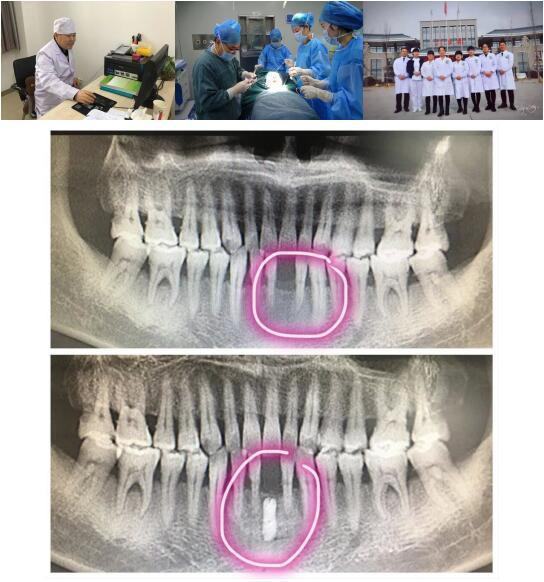

啄木鸟 高陵院区口腔科成功开展一例GBR引导骨再生技术种植牙